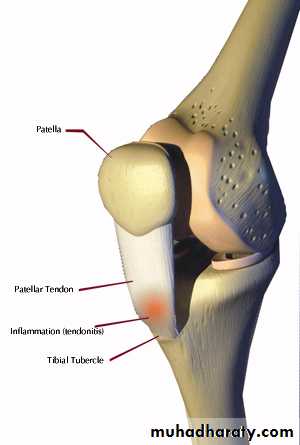

INJURIES

OsgoodSchlatter's disease